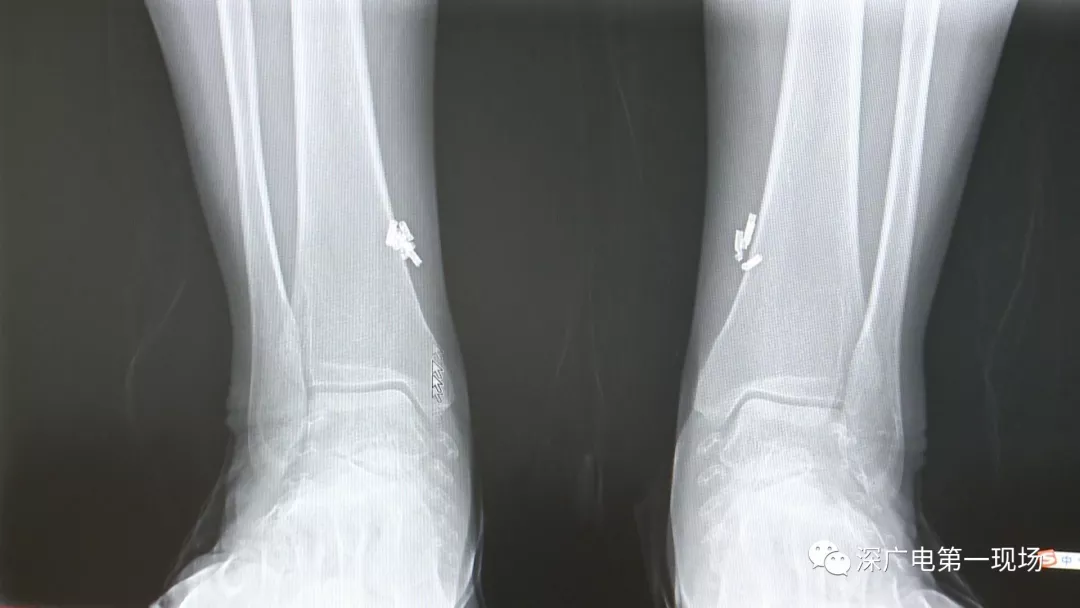

深圳一女子全身被植入彈簧圈,數(shù)量多到驚人!竟是為治這病…

出于保護(hù)患者,我們沒(méi)有直接采訪,但是通過(guò)醫(yī)生的介紹,記者了解到,病人是個(gè)36歲的女性,2歲開(kāi)始就有癲癇病史,而且藥物治療也并不見(jiàn)效。

多方打聽(tīng)之后,在山東某診所用全身埋彈簧圈的方式治療癲癇。陶主任介紹,這樣的方式想要治愈,那幾率也等同于撞大運(yùn)?。?/p>